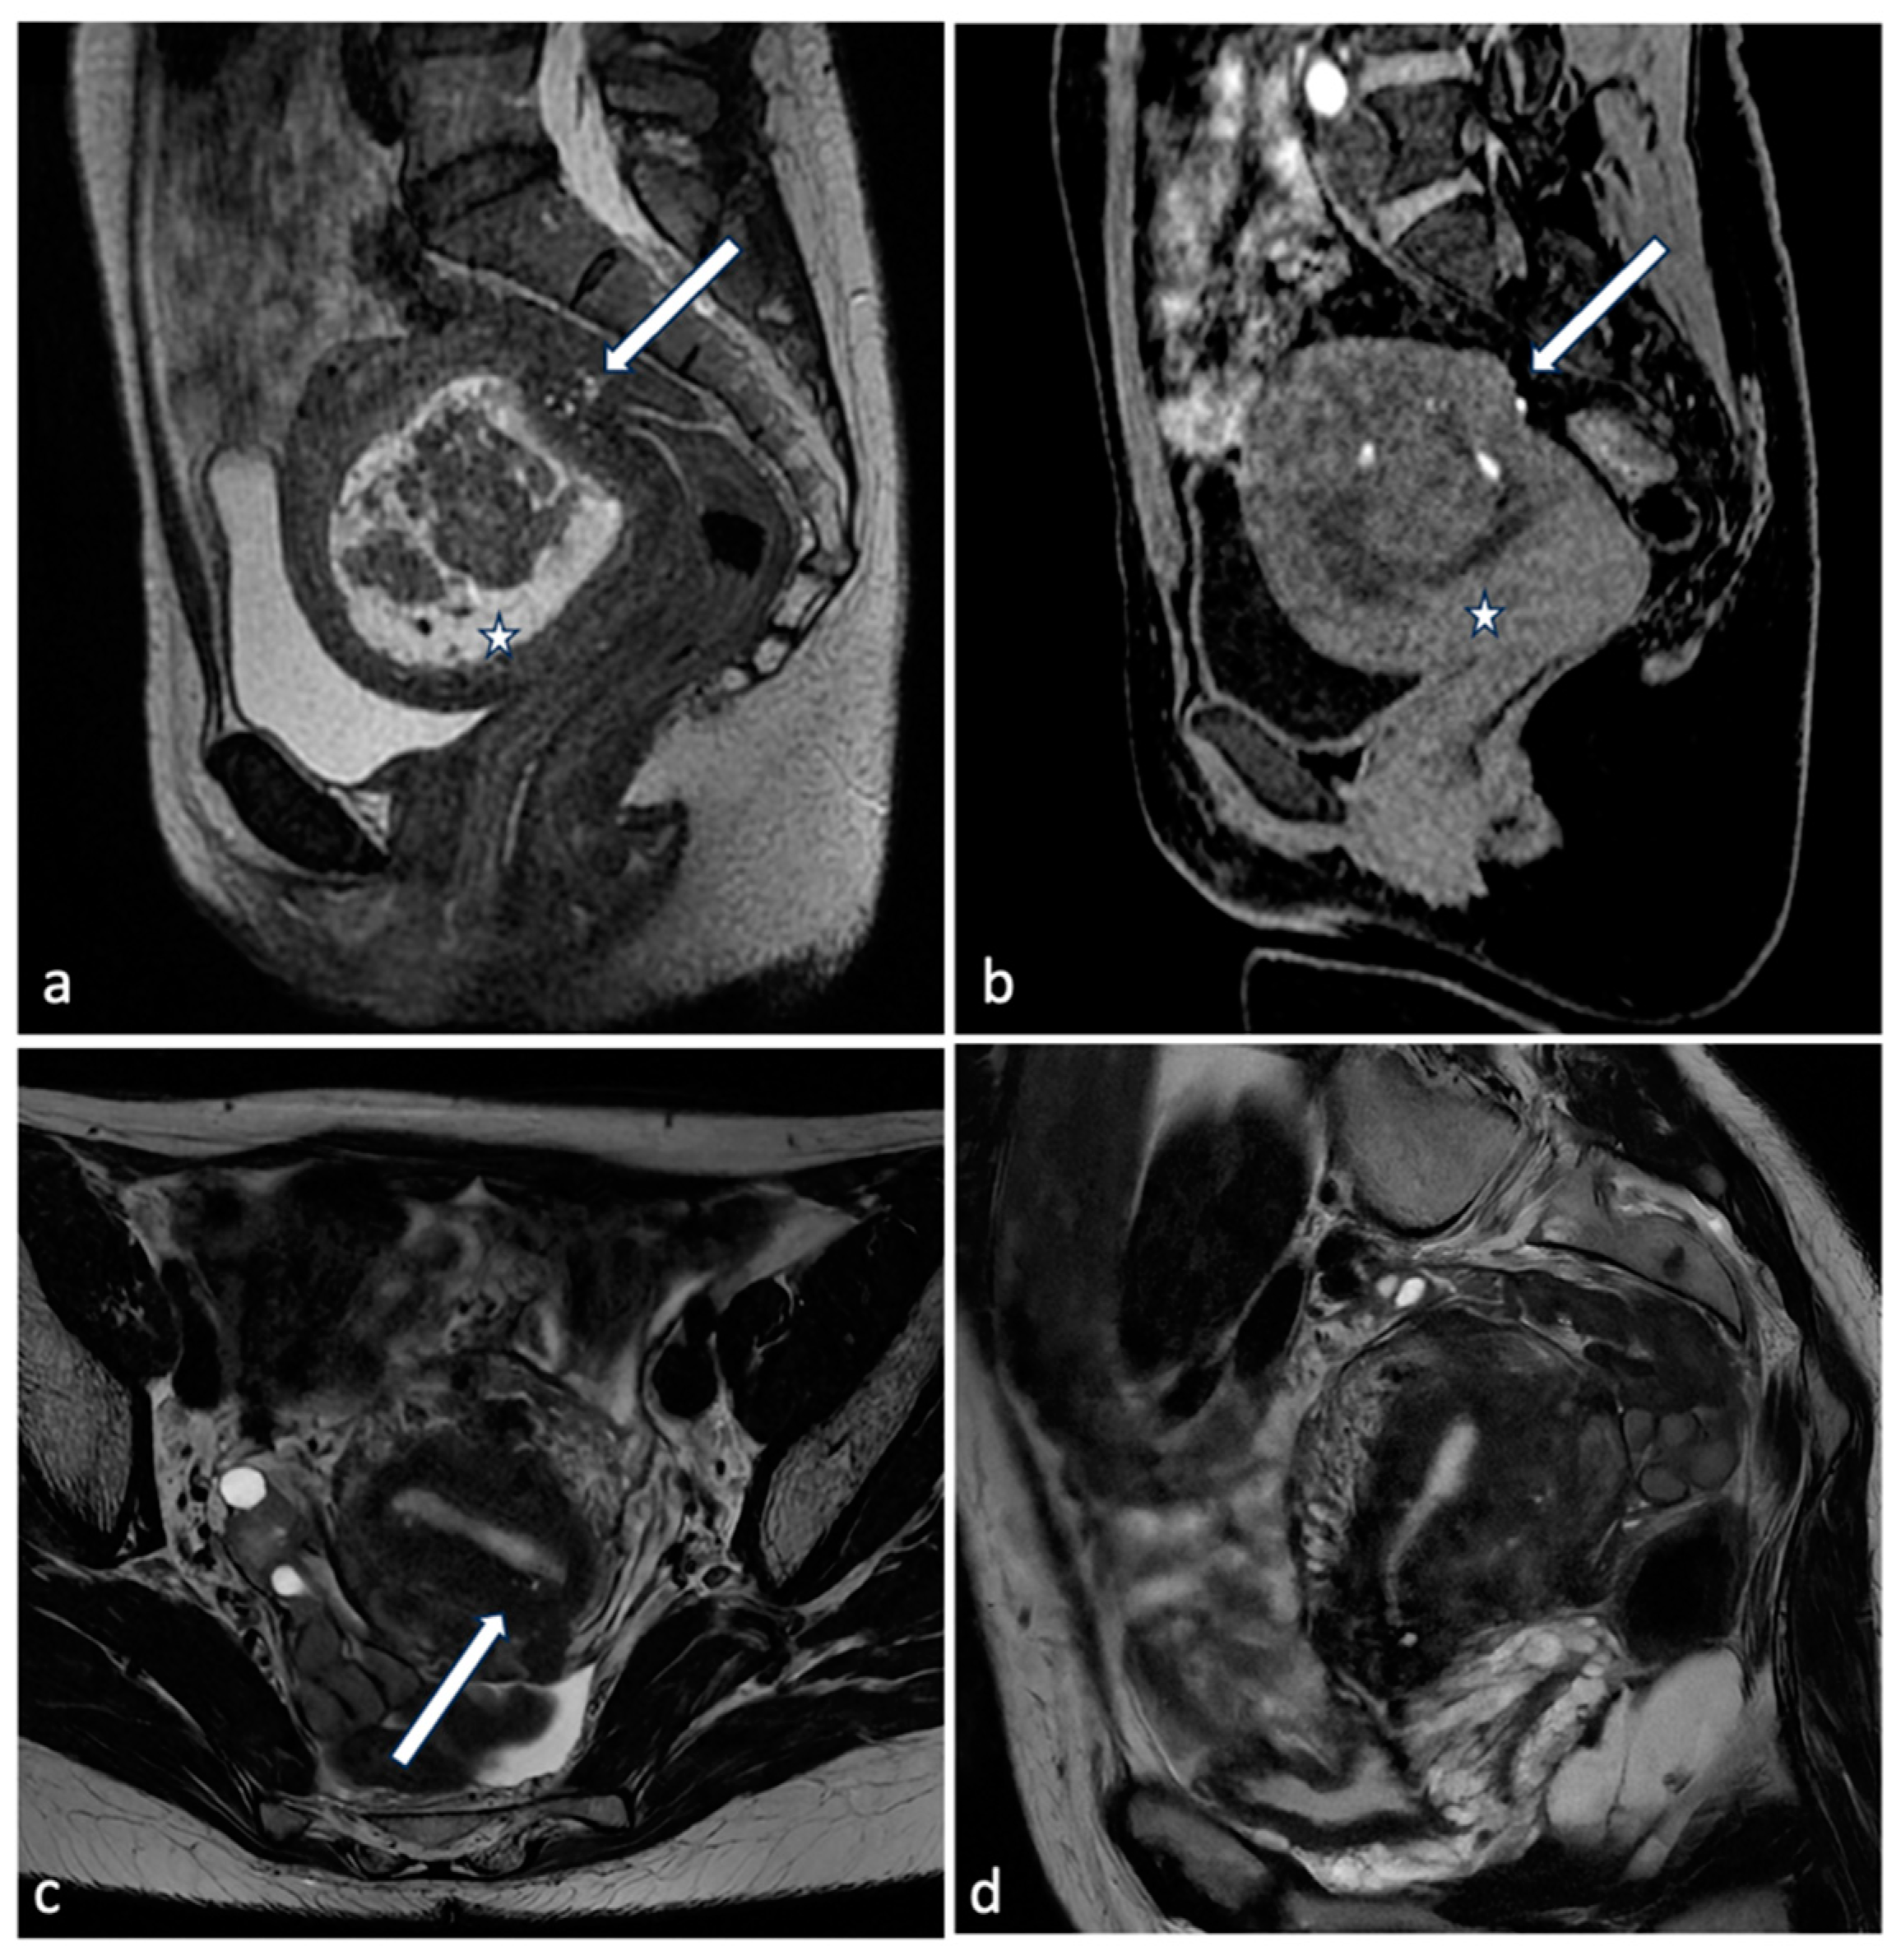

Figure 4.

Uterine artery embolization for leiomyoma. A 27-year-old patient presenting with menometrorrhagias and pelvic pain. TVUS and MRI demonstrated a voluminous isthmic uterine leiomyoma (12 cm of diameter). Selective left uterine artery arteriogram (a) shows multiple vessels feeding the large leiomyoma. Embolization through the release of embolizing microparticles was performed. Post-embolization left artery arteriogram (b) shows good devascularization of the leiomyoma. Post-embolization selective right uterine arteriogram (c) showed ectasia of the right tubal artery with origin of tubo-ovarian trunk for the ipsilateral annexal branches. Given the high risk of non-target embolization, embolization of the right uterine artery was not performed.